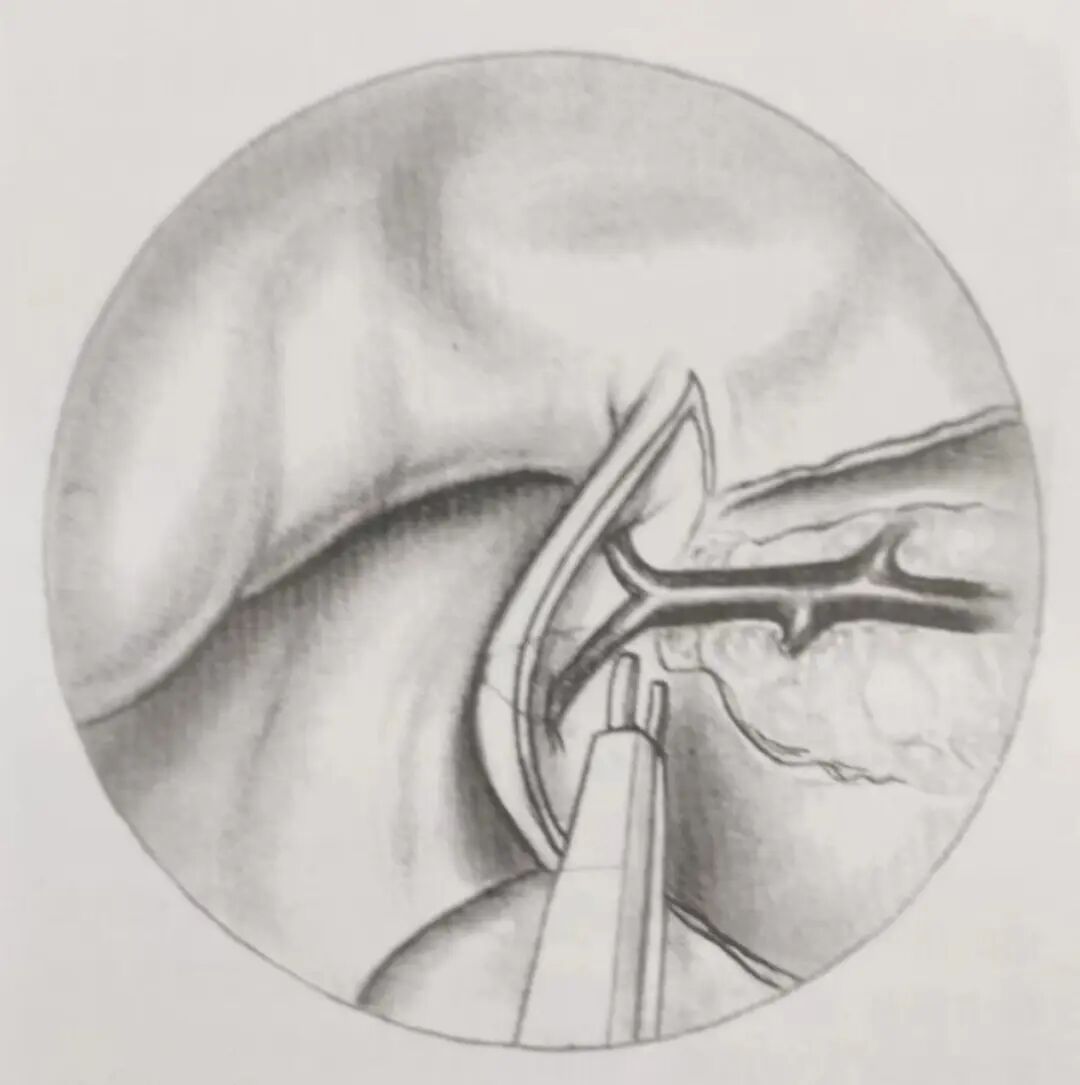

使用内镜自下而上检视鼻腔,可观察到蝶腭孔处蝶筛动脉隆起(图10)。在蝶腭孔的前下方可观察到筛骨嵴(一个小的骨嵴)。蝶腭孔位于上颌窦的后上角。打开大的开窗的优点包括:在手术分离时避免蝶腭动脉的直接损伤,便于发现血管近端分支出现的多个穿支小血管,为吸引器(第三只手)放置提供空间。

图10右侧蝶腭动脉的内镜下所见,位于该动脉的蝶腭孔出口位置

一旦黏膜下小袋形成,可放置一个吸引器于袋内,以保持术区无血。牵引蝶腭动脉横跨术区。使用1mm克氏咬骨钳咬除蝶腭动脉上方蝶腭孔周围骨质(图11)。

图11小孔由咬骨钳扩大,为了显露蝶腭动脉的主要分支